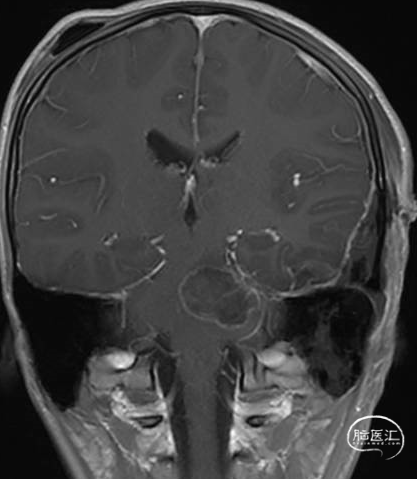

术后MRI

术前MRI